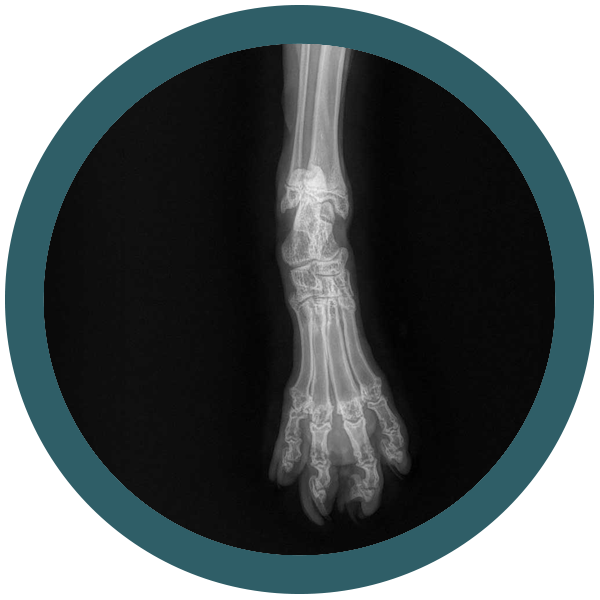

Il tuo gatto è un compagno fedele e amorevole che ti dà gioia ogni giorno. Ma anche i gatti possono soffrire di problemi ortopedici.

La buona notizia è che ci sono molti modi per prevenire i problemi ortopedici nei gatti. Una dieta sana e nutriente, esercizio fisico quotidiano e controlli regolari dal veterinario possono aiutare a mantenere il tuo gatto in forma e sano. Ma cosa succede se il tuo gatto ha un problema ortopedico? In questo caso interveniamo noi di Ortovet.

Siamo una rete di specialisti ortopedici veterinari e offriamo un servizio di elevata qualità, con l’utilizzo delle tecniche chirurgiche più avanzate. I nostri medici veterinari sono esperti nel trattamento di una vasta gamma di problemi ortopedici nei gatti

Osteocondrodisplasia Scottish Fold: quando la dolcezza delle orecchie nasconde un problema serio